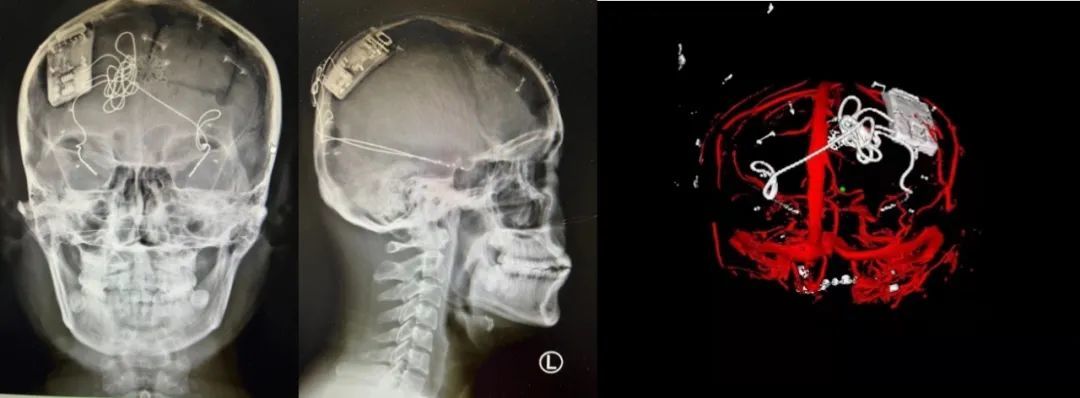

本次手術(shù)過程順利,術(shù)中刺激器各項(xiàng)指標(biāo)均工作正常,術(shù)后重建顯示電極位置精準(zhǔn),腦電信號(hào)清晰?;颊邽槟行?,入院后診斷為雙側(cè)顳葉癲癇,此類癲癇為開顱手術(shù)的相對(duì)禁忌癥,在藥物無法控制的情況下,傳統(tǒng)治療效果欠佳 。

團(tuán)隊(duì)根據(jù)術(shù)前計(jì)劃,在手術(shù)機(jī)器人輔助下完成雙海馬長(zhǎng)軸電極及 IPG 植入,術(shù)后重建顯示電極位置精準(zhǔn),腦電信號(hào)清晰。術(shù)后第二天,患者即下床活動(dòng),身體狀況恢復(fù)良好。